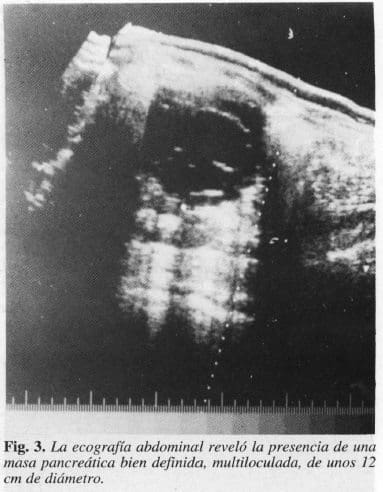

La radiografía simple del abdomen mostró una masa en el epigastrio, radiopaca y redondeada; la serie gastroduodenal demostró rechazo del estómago hacia adelante y a la derecha (Figs. 1 y 2); la ecografía abdominal reveló la presencia de una masa pancreática bien definida, multiloculada (Fig. 3). (No se pudo realizar la T.A.e. del abdomen por falta de recursos económicos de la paciente y de la institución). En vista de la historia clínica anterior, fue llevadaa cirugía con la impresión diagnóstica de tumor quístico verdadero del páncreas. Durante el acto operatorio seencontró una masa de aproximadamente 12 cm de diámetro de consistencia dura, no adherida a los órganosadyacentes, móvil, que comprometía la porción distal del cuerpo y la cola del páncreas. Se observó que las anastomosis hechas en las operaciones anteriores estaban ocluídas, por lo que se procedió a practicar resección de la masa con pancreatectomía distal de la cola del páncreassin esplenectomía (Fig. 4); toleró el acto operatorio y no hubo complicaciones. La estancia hospitalaria fue de 10días; la evolución posquirúrgica igualmente satisfactoria. Informe anatomopatológieo: Masa quística multiloculada de 12 cm de diámetro con septos delgados, líquido seroso hemorrágico; al microscopio, epitelio monoestratificado cuboidal, sin proyecciones papilares, tejido glandular adyacente normal (cistadenoma seroso del páncreas) (Fig. 5).

La radiografía simple del abdomen puede mostrar calcificaciones en un 10 a 18% de los casos (8) y hasta el 38% en cistadenomas mucinosos y el 16% en los serosos (7); en nuestra paciente se visualizaba una imagen radiopaca, redondeada y sin calcificaciones. La serie radiológica gastroduodenal define la presencia de una masa extrínseca que rechaza el estómago y el marco duodenal. Utilizada en otros tiempos, lioy ha sido remplazada por la TAC, la cual presenta una mejor definición y mayor extensión de la masa; en la arteriografía celíaca y de la mesentérica superiorhay hipervascularidad a diferencia del pseudoquisteque es hipovascular con desplazamiento y estiramiento de los vasos (1, 8, 12, 14, 16, 17). El advenimiento de la tecnología ha permitido el uso de la ecografía abdominal, método diagnóstico no invasor, fundamental en nuestro medio por su fácil acceso, gran resolución, que demuestra la masa bien definida, ligeramente irregular, con numerosos ecos internos por los tabiques de los quistes multi1oculados (7-9, 15); fue el medio diagnóstico más útil para sospechar la patología del presente caso.